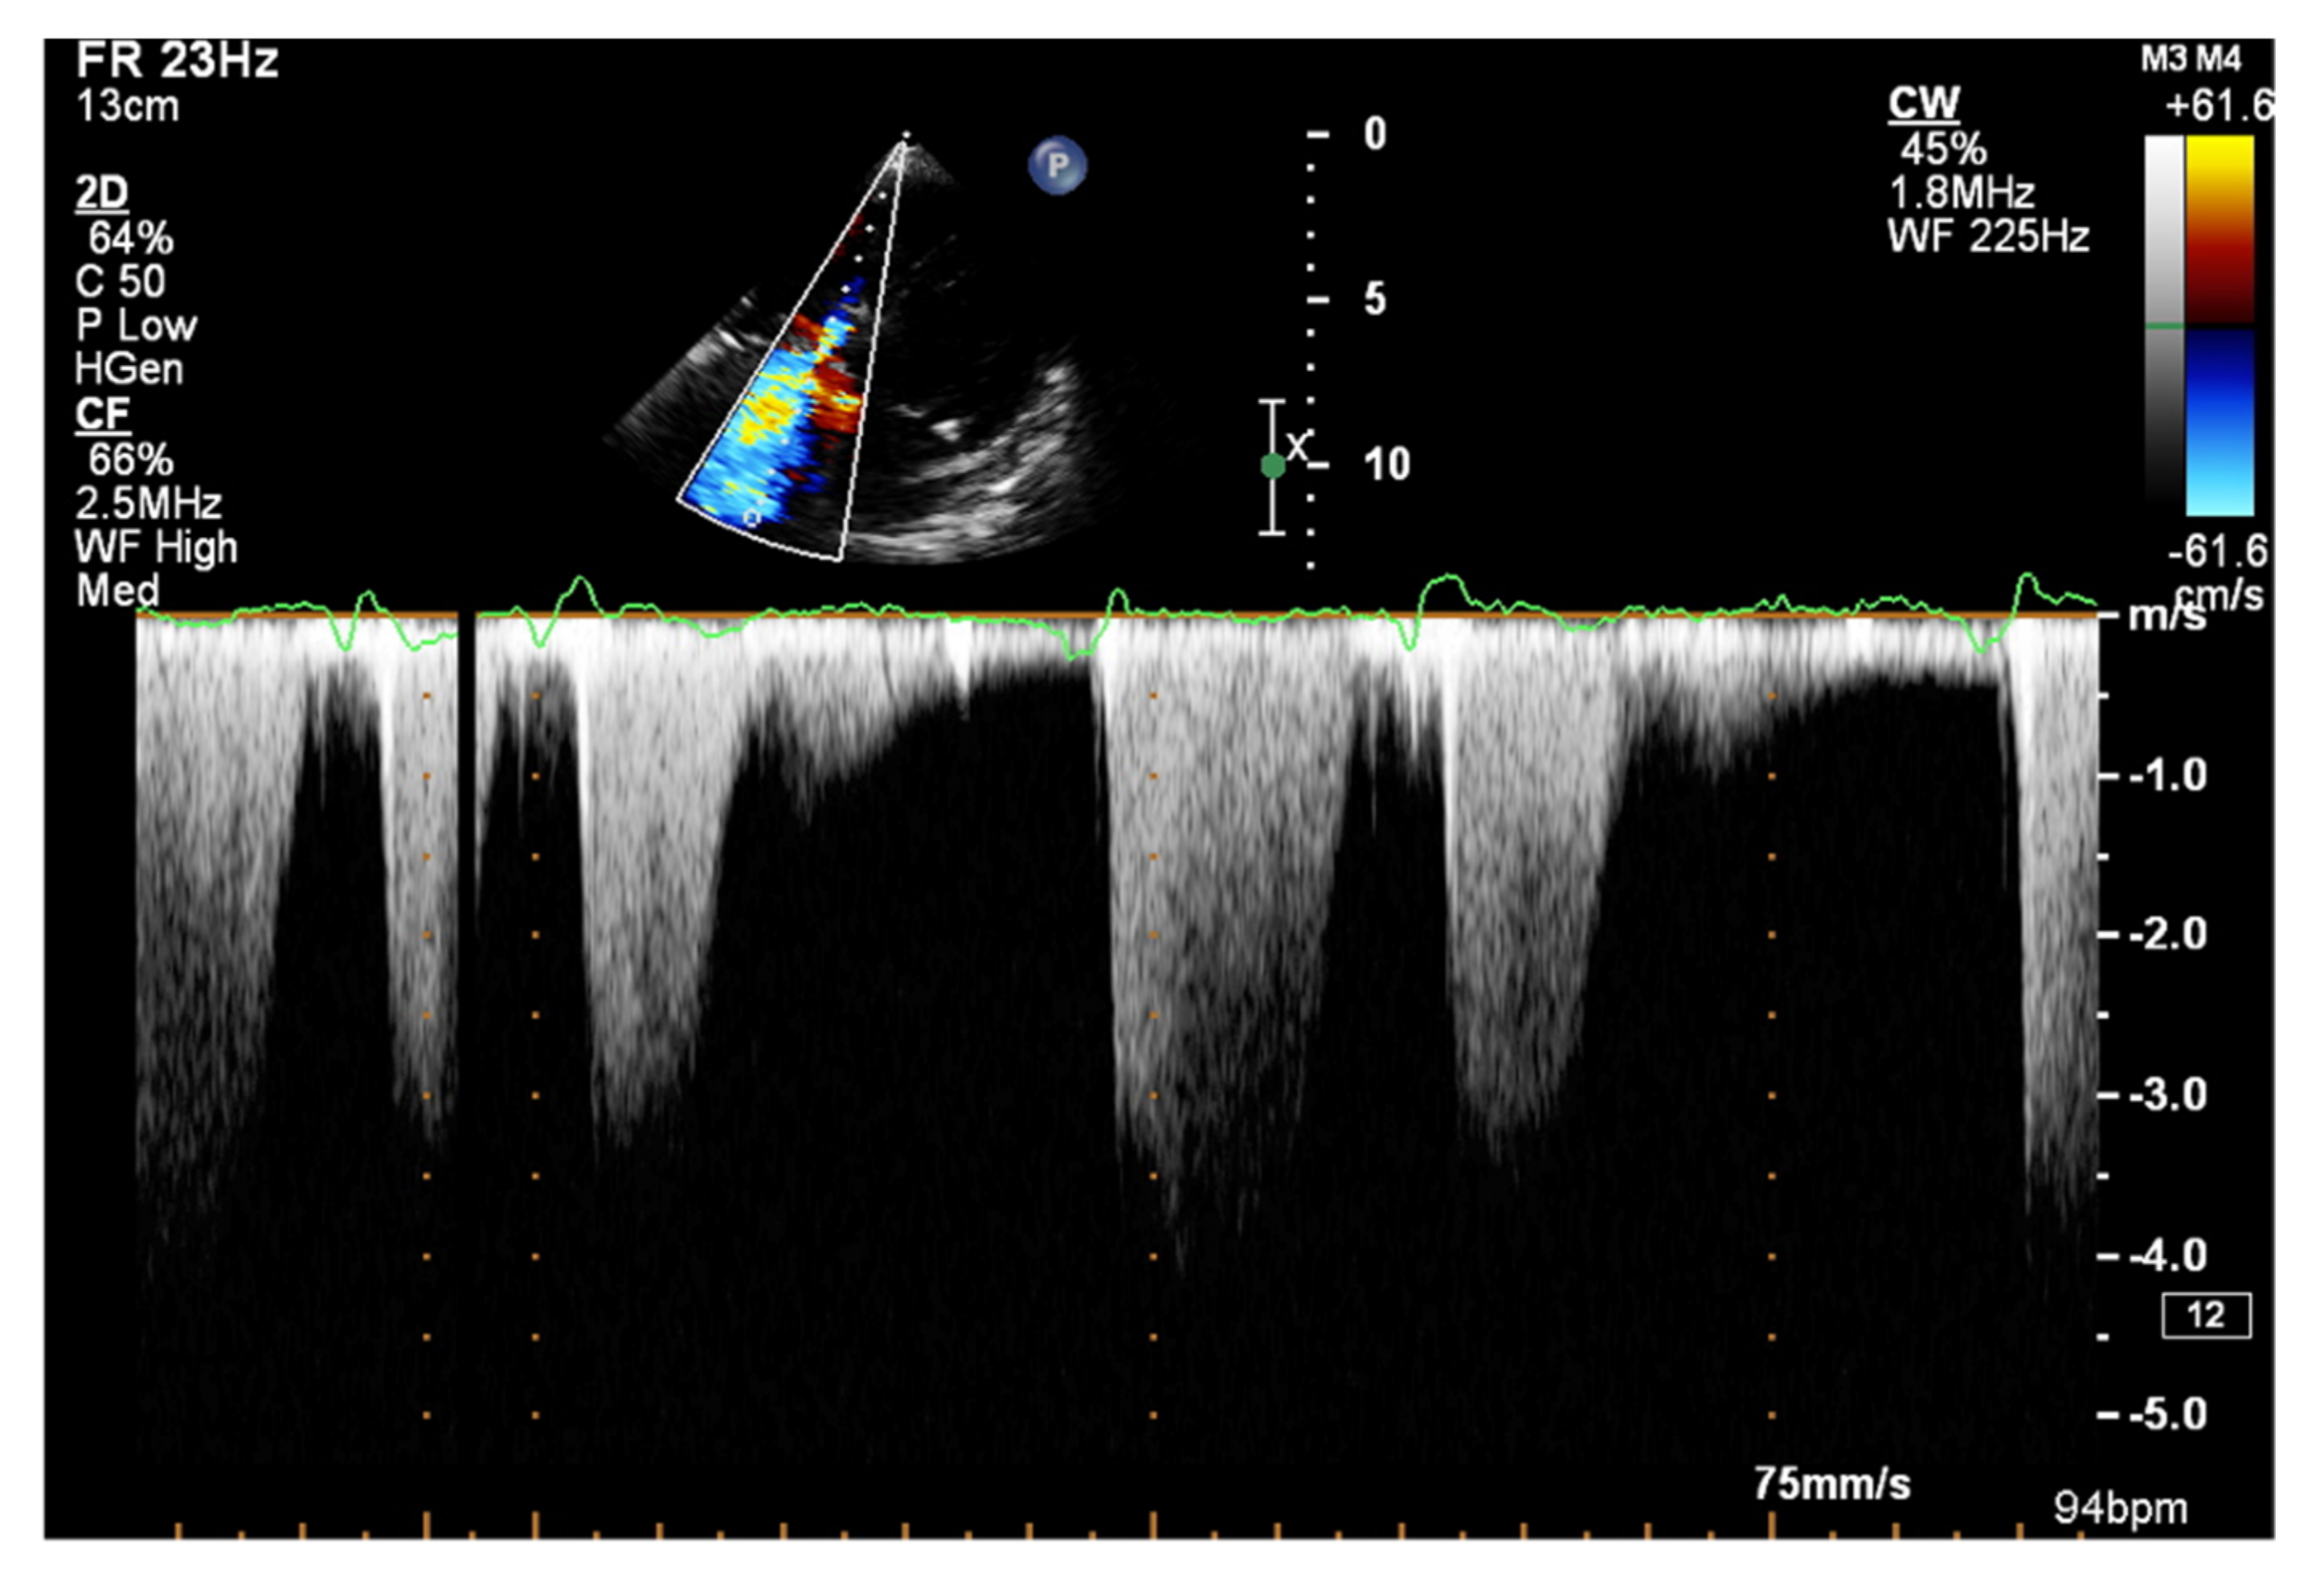

It is believed that if there is no RV outflow tract stenosis, the right ventricular systolic pressure (RVSP) is equal to the pulmonary artery systolic pressure (PASP) [70]. In everyday practice, the calculation of PASP is based on a simplified Bernoulli equation applied to peak tricuspid regurgitation velocity (TRV). TRV should be measured in several views, aiming at the best image quality and maximum velocity in continuous-wave Doppler and avoiding excessive gain and artifacts (Figure 12 and Figure 13). According to the equation, PASP = 4 (TRV)2 + RAP [71,72]. In addition, based on the measurements of end-diastolic pulmonary regurgitant return wave velocity (PRVend), it is possible to estimate pulmonary artery diastolic pressure (PADP) using the PADP = 4 (PRVend)2 + RAP formula [73]. On the other hand, PASP and PADP values can be used to calculate approximations of mean pulmonary artery pressure (mPAP) using the mPAP = 1/3 (PASP) + 2/3 (PADP) formula [74]. Several other formulas for calculating mPAP can be found in the literature. Chemla et al. developed another method to calculate mPAP, according to the formula mPAP = 0.61 × PASP + 2 mmHg [75].

Figure 12.

Doppler assessment of tricuspid regurgitant velocity (TRV). TTE, 4CH view. TTE: transthoracic echocardiography; 4CH: four-chamber.